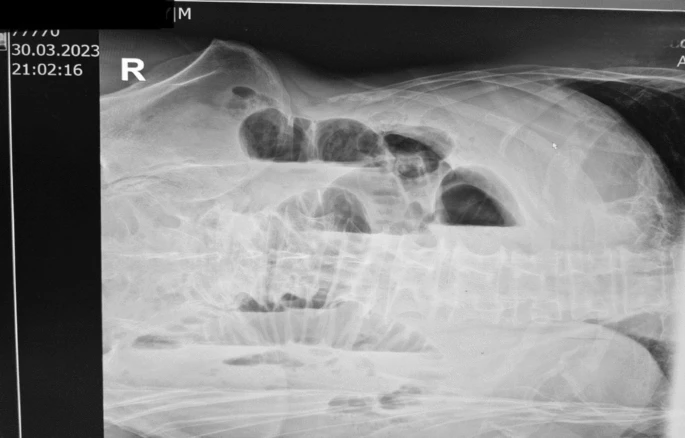

The patient was referred for an abdominal X-ray. The X-ray of the abdomen in the left lateral decubitus position showed prominently shaped loops of the small intestine with air–fluid level. It is indicative of dilated loops of the small intestine, suggestive of ileus